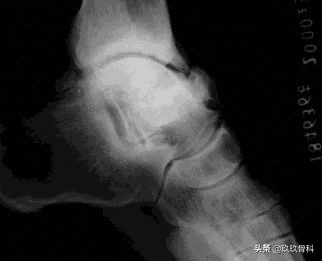

运动员踝关节的骨关节病▲▲▲

名称:运动员之踝、足球踝、踝关节撞击性骨疣、踝关节前撞击综合征

原因:

- X线显示的骨疣骨唇均在关节内与关节囊和韧带无关

- 关节内骨疣、骨唇以及骨的改变